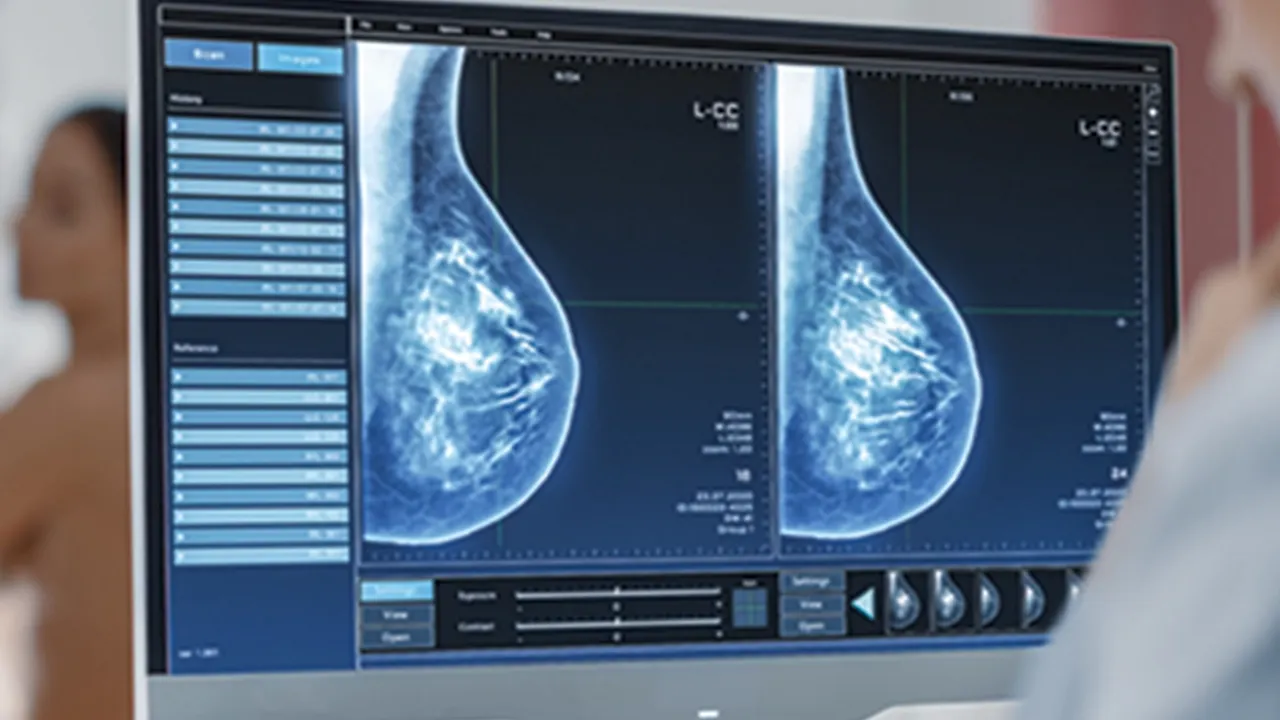

Meme kontrolünün nasıl olması gerektiğini anlatan Poçan, “Memedeki problemleri tespit etmek için yaş fark etmeksizin, kendi kontrollerimizi aksatmamalıyız. Kontrollerde bir problem tespit ettiğimizde ya da kırk yaş üstünde ise bir hekim tarafınca kontrol, meme ultrasonu, gereklilik halinde mamografi veya meme MRG ile tetkikleri gerekmektedir. Ülkemiz sağlık politikalarınca mamografi ön planda tutulsa da teknolojik gelişmelerin ultrason cihazlarında yapmış olduğu belirgin gelişim nedeniyle meme ultrasonu ile değerlendirme hem güvenilir hem de değerlidir” dedi.

Meme Ultrasonu, Mamografi ve Meme MR’ı hakkında da bilgiler veren Dr. Poçan, “Her üç yöntem de meme kanseri taramasında önemli rol oynar, ancak uygulama durumuna, hastanın özelliklerine ve risk faktörlerine göre tercih edilir” şeklinde açıklamalarda bulundu.